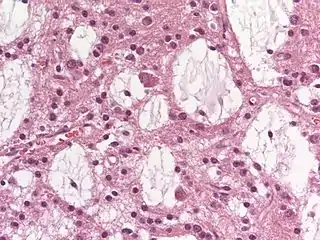

Es parecido a un oligodendroglioma, pero con neuronas visibles.[4] Está inserto en el Grado 1 de la clasificación de tumores cerebrales de la OMS y, generalmente, tiene muy buen pronóstico.[5][6] Macroscópicamente, los tumores son suaves y gelatinosos. Los tumores se pueden formar varios nodos en la corteza y, ocasionalmente, en la cubierta de la sustancia blanca (sustancia blanca) . La región más afectada del cerebro, el lóbulo temporal , seguida por los lóbulos frontales y menos frecuentemente a partir de la corteza parietal . Microscópicamente, la característica más importante es una estructura compleja que consta de glia y neuronas (elementos de los llamados elementos glioneuronal ). Los elementos gliales son filamentos de fibras gliales y vasos sanguíneos. Ellos definen "los lagos de moco", que son en gran medida neuronas maduras.